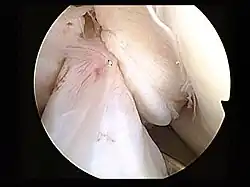

Arthroscopie

L'opération proprement dite commence par l'introduction de l'arthroscope dans le genou du patient. Ceci permet de confirmer définitivement le diagnostic de rupture de LC. Les autres blessures, en particulier celles des ménisques, peuvent être soignées avant la reconstruction du LC.